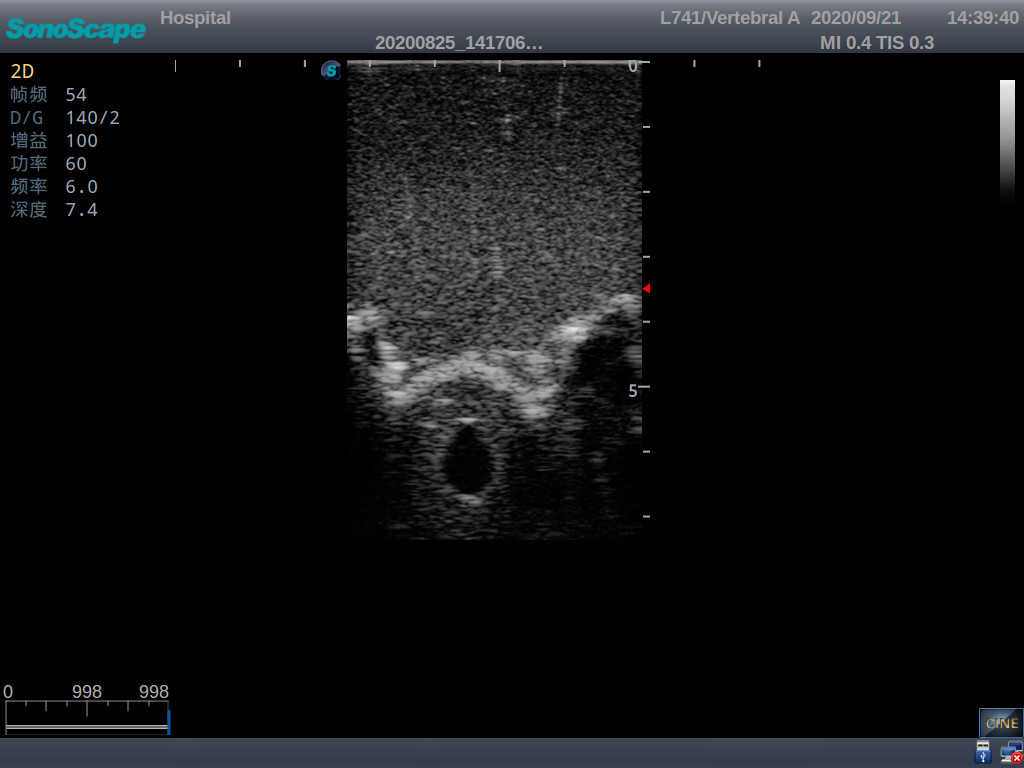

Model TYE1549.2

This model is an ideal choice for ultrasound-guided adult lumbar puncture training with true-to-life skin feel and touch, accurate anatomical structures as well as real clinical ultrasound images. Realistic resistance to needle tips and correct landmarks provide excellent hands-on experience.

· Realism:

1)  Advanced material for true-to-life skin touch, feel and puncture

2)  Real clinical ultrasound images

3)  Compatible with various real ultrasound machines